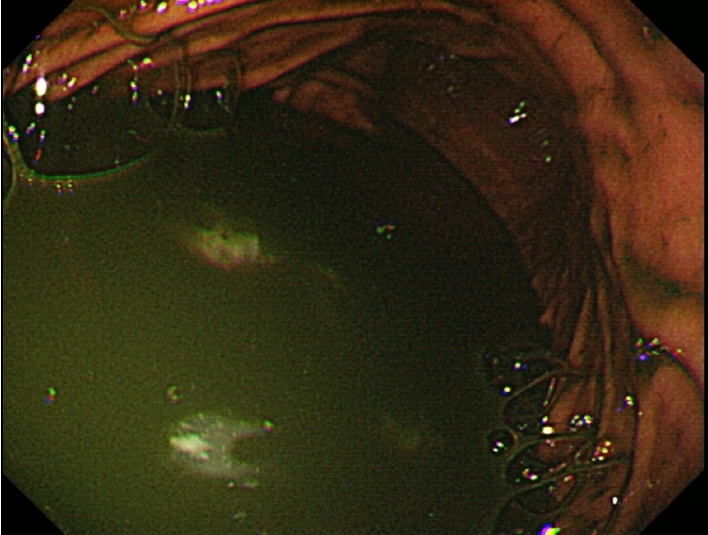

Figure 2.

Gastroscopy showing retained bile juice and gastric contents in the body.